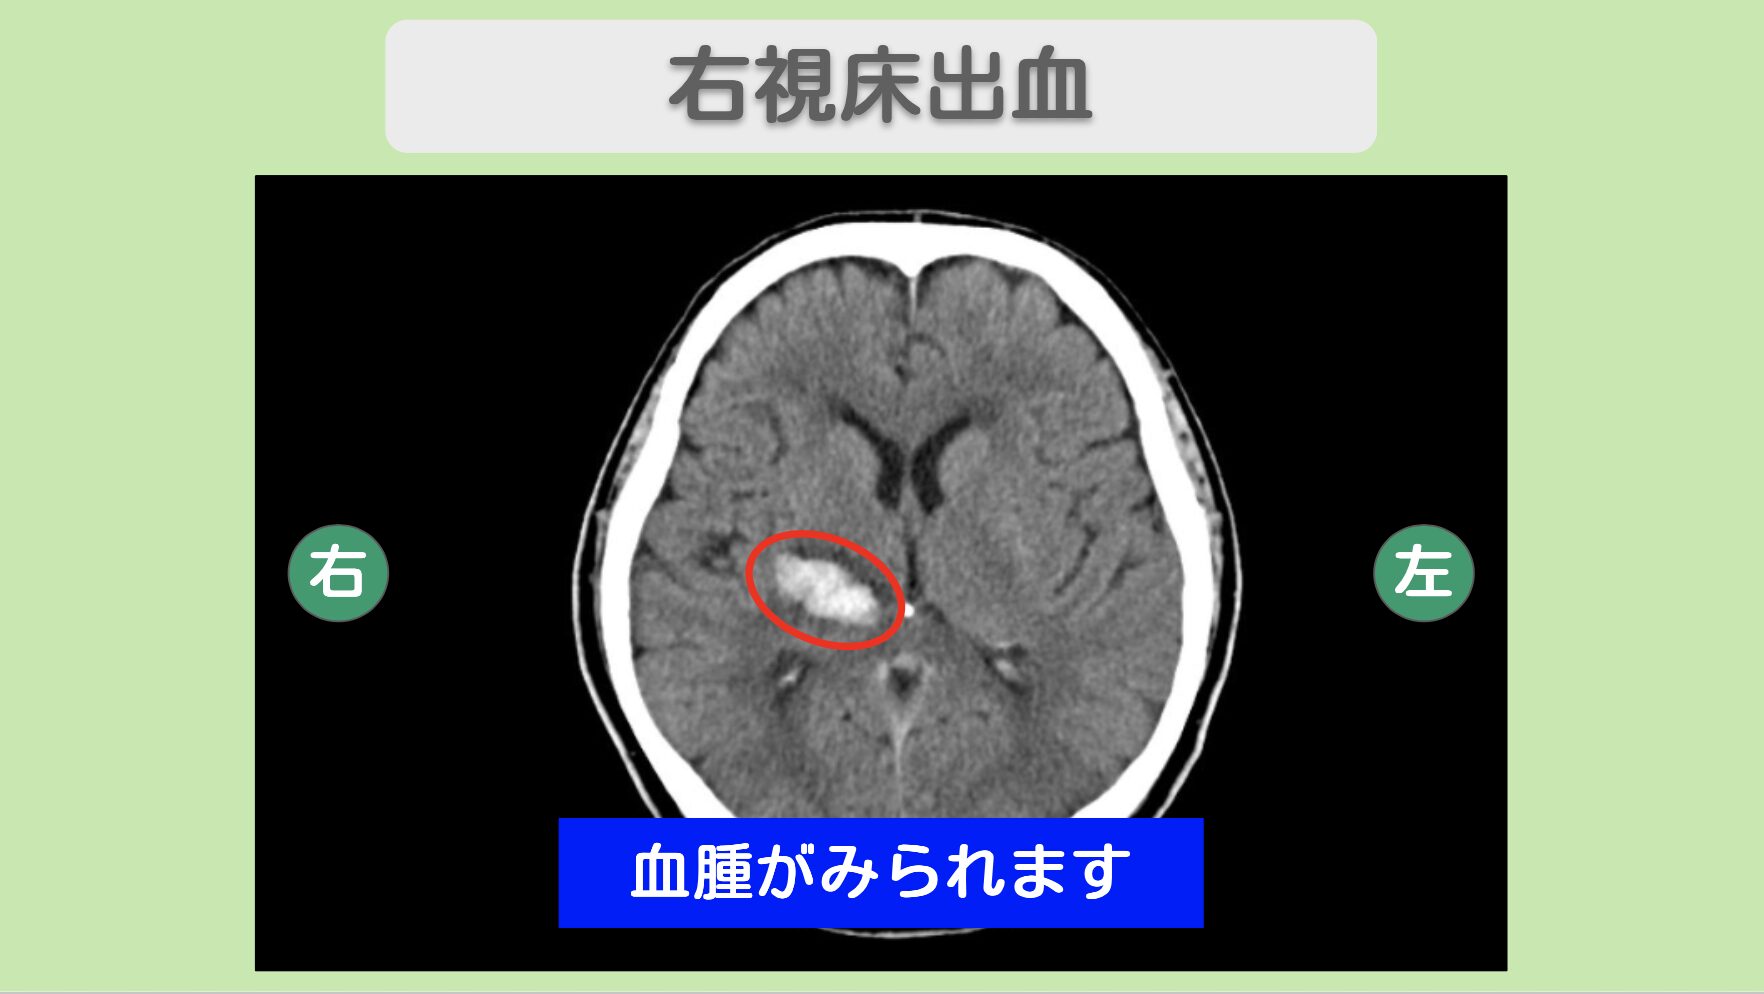

- 脳出血(右視床出血)と診断され、血腫は約3cmで脳の深部に位置していた

CT所見